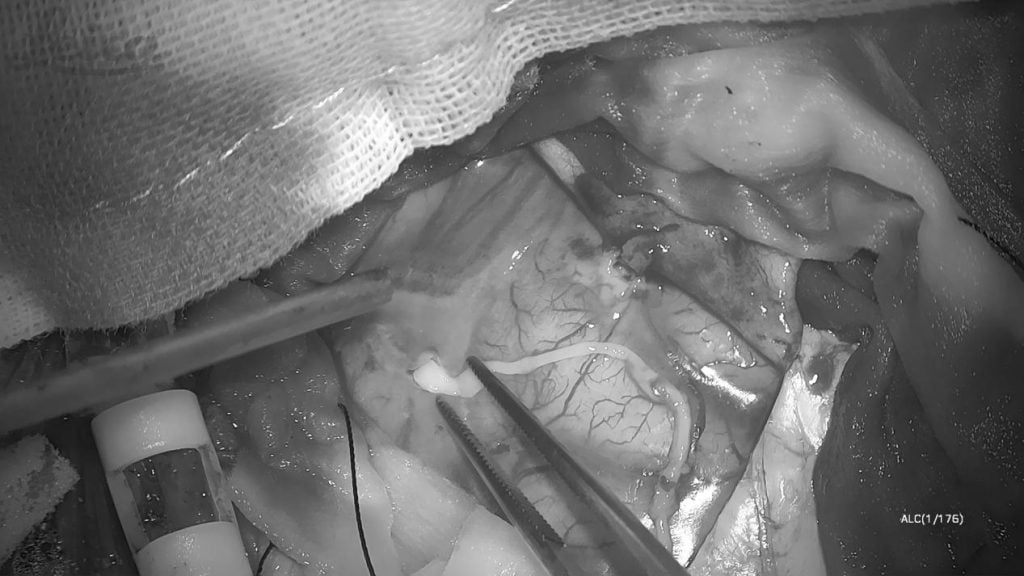

手术当天,医护团队先在全麻状态下完成开颅。当暴露病灶区域时,麻醉科医生逐步调整用药,将林浩从麻醉中唤醒。

“能听见我说话吗?试着睁睁眼。”林浩根据指令吐舌、握拳、回答简单问题。通过实时互动,张旭标精准定位功能区边界,并成功捕获一条约10公分长,仍在蠕动的裂头蚴。